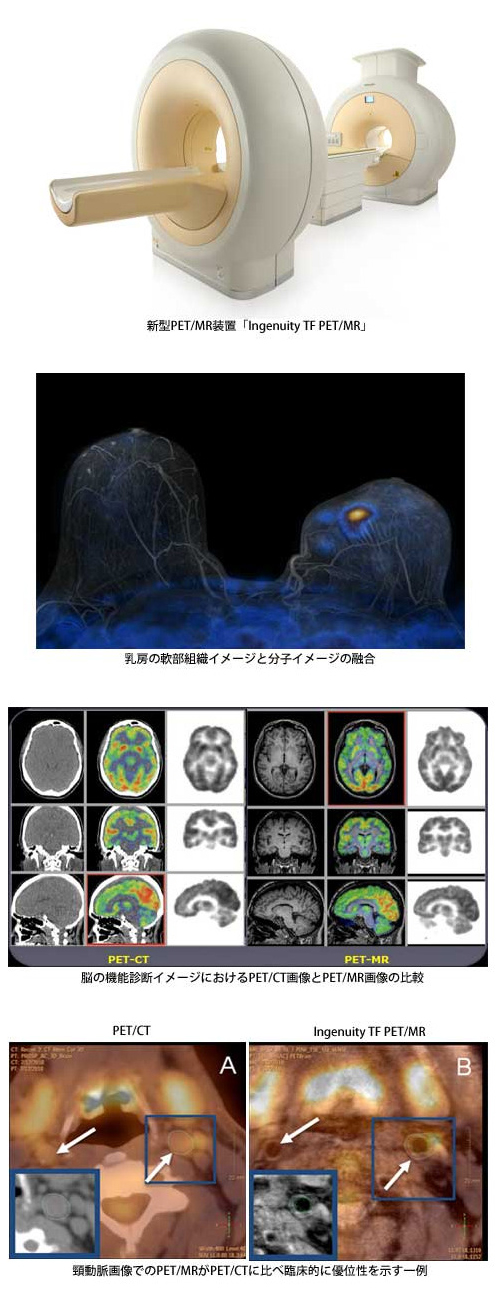

株式会社フィリップス エレクトロニクス ジャパン(本社:東京都港区、代表取締役社長:ダニー・リスバーグ、以下 フィリップス)は、本日より、PET(陽電子放射断層撮影)装置とMRI(磁気共鳴画像診断)装置を融合させたPET/MR装置「Ingenuity TF PET/MR」(インジェニュイティー・ティーエフ・ペット/エムアール)の販売を開始することを発表しました。本装置はグローバルで開発した、フィリップス初のPET/MR装置となります。

この「Ingenuity TF PET/MR」は、PET装置とMRI装置双方の最高水準の性能と画質を損なうことなく融合させた、新しいハイブリッドシステムです。PET部分はAstonish TF Time-of-Flight technology*1を搭載し、高速スキャン、ポジトロン核種投与量低減/低被ばく、高画質を実現し、MRI部分は、フィリップス独自のMultiTransmit*2技術で3.0T高磁場の不均一さを向上させた高性能MRI装置「Achieva 3.0T TX」(アチーバ・3テスラ・ティーエックス)をベースとしています。これらフィリップス独自の最高水準の技術を搭載したPET、MRI両装置を融合させた「Ingenuity TF PET/MR」は、いかなる患者様でも安定した高画質の全身画像を提供することができます。

「Ingenuity TF PET/MR」は、すでに欧米で全身を対象にNeurology(脳神経)、Cardiology(心臓)、Oncology(腫瘍)分野での臨床を開始しております。また、従来のPET/CTに比べ低被ばくを実現しながら、MRIによる形態画像と機能画像が可能な新しい分子イメージングシステムとして、より高い診断能を引き出す研究も行われています。